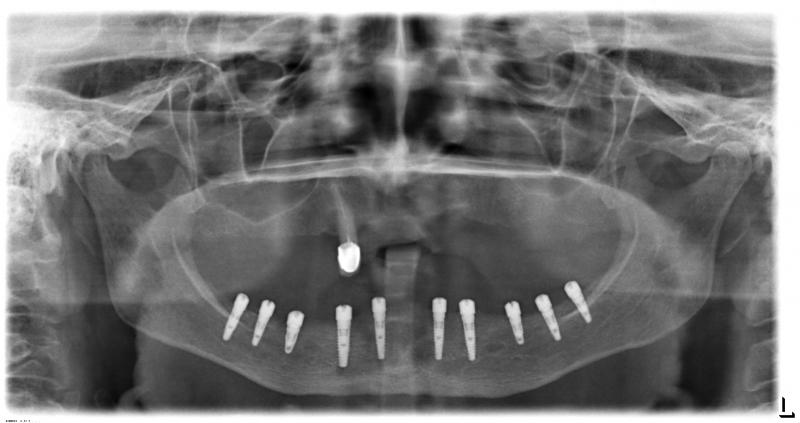

Установка 10 имплантантов на беззубую челюсть с помощью компьютерной программы: Через месяц после удаления